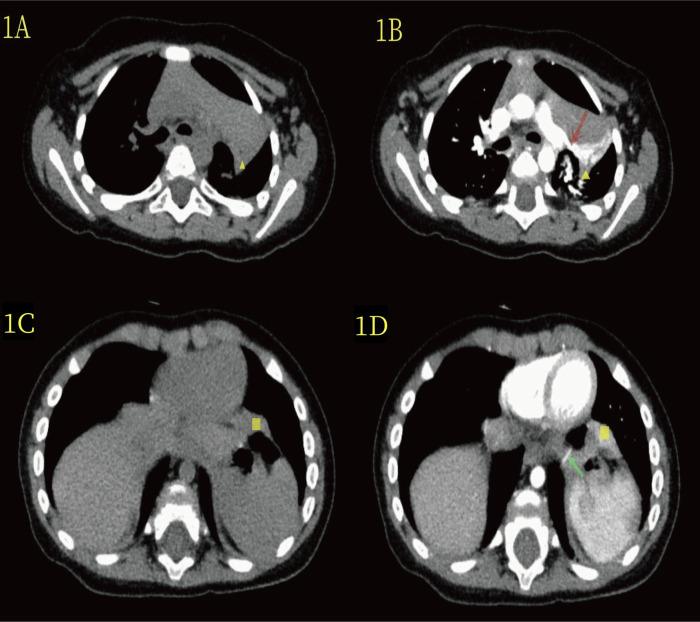

Reports of bronchopulmonary sequestration in two or more locations within the ipsilateral thorax in children are rare. To date, only a few clinical reports have described thoracoscopic two-port treatment for external lobe bronchopulmonary sequestration. We performed thoracoscopic two-port surgery on a 7-month-old girl and identified two abnormal masses in the left thoracic cavity: one located in the upper hilum of the lung and the other on the surface of the lower diaphragm. Both masses were resected using two-aperture thoracoscopic surgery and were pathologically confirmed as extralobar bronchopulmonary sequestrations. Preoperative computed tomography (CT) only detected the lesions in the upper hilum of the lung, indicating that CT alone is insufficient to achieve a comprehensive and accurate diagnosis of the disease in similar cases. Therefore, the thoracoscopic two-port technique can better diagnose and treat these diseases.

儿童同侧胸腔内两个或更多部位发生支气管肺隔离症的报道很少见。迄今为止,仅有少数临床报告描述了胸腔镜两孔法治疗叶外型支气管肺隔离症。我们对一名7个月大的女童进行了胸腔镜两孔手术,在左侧胸腔内发现了两个异常肿块:一个位于肺门上部,另一个位于膈肌表面。两个肿块均采用两孔胸腔镜手术切除,病理证实为叶外型支气管肺隔离症。术前计算机断层扫描(CT)仅检测到肺门上部的病变,表明在类似病例中,仅靠CT不足以对该疾病进行全面准确的诊断。因此,胸腔镜两孔技术能够更好地诊断和治疗这些疾病。